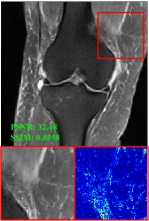

Figure 5 provides the qualitative comparison of the various methods on the four datasets at a scale of 4. The top, second, third, and bottom rows are the SR results under the FastMRI, clinical brain, clinical tumor and clinical pelvic datasets, respectively. The red boxes indicate the zoom-in region of complicated anatomical structures along with their corresponding error maps. Note that the brighter textures in the error maps, the lower the quality of the reconstructed images. As can be seen, compared to methods based on Transformers and CNNs, diffusion-based methods like DisC-Diff and DiffMSR (Ours) are capable of reconstructing high-realistic images with promising reconstruction metric scores (PSNR and SSIM). Nevertheless, while DisC-Diff can reconstruct high-precision MR images, it does not preserve the structure present in the original HR images, introducing some additional information that can affect medical diagnosis. In contrast, our method combines DM and PLWformer, which can preserve the original image’s structure while restoring high-frequency information.

In this section, we present more visual qualitative comparisons. Figures 8, 9, 10, and 11 show the reconstruction results of each method in FastMRI, clinical brain, clinical tumor, and clinical pelvic, respectively. As can be seen, although DisC-Diff can reconstruct MR images with high-frequency information, it fails to preserve the structure and content of the original Target HR image effectively, resulting in image distortion. In contrast, our proposed DiffMSR can restore high-frequency information while preserving the structure of the original HR image, indicating the effectiveness of the joint use of DM and PLWformer.